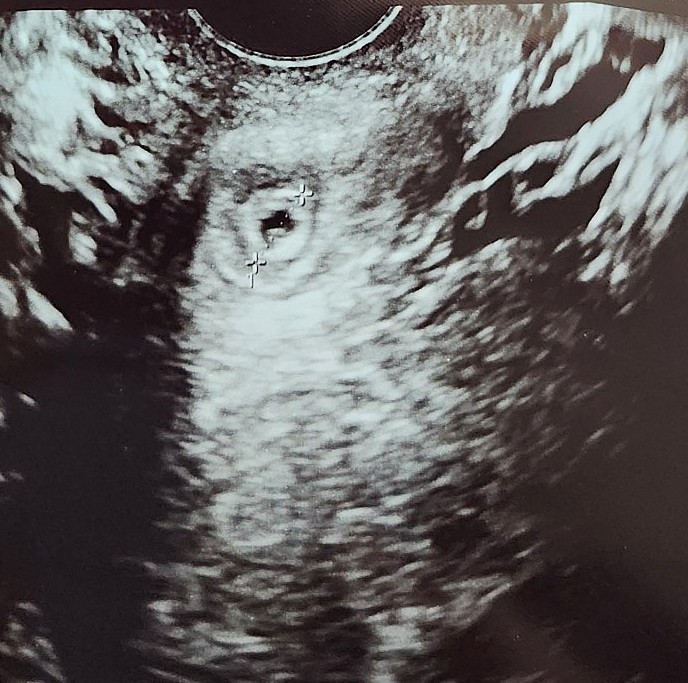

태아 임신 난황 위치성별 시기, 아기집 보이는 시기, 아기 심장소리

아기가 생기고 초기에는 배가 나오지 않는데다 별다른 증상도 없었기에 임신을 실감하기 어려웠는데요, 주...